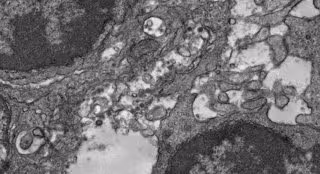

Archivo - Imagen de microscopía electrónica del tejido de un ganglio linfático de un ratón que fue inmunizado con esta vacuna experimental contra la COVID-19.

Archivo - Imagen de microscopía electrónica del tejido de un ganglio linfático de un ratón que fue inmunizado con esta vacuna experimental contra la COVID-19. - YI-NAN ZHANG - Archivo